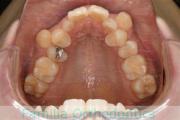

口元に力が入ってしまうのを治したいということで来院されました。上の側切歯が小さいのですが、しっかり前歯を後退させたいということで。上下左右から小臼歯を抜歯してマルチブラケット法にて治療を行い、移動後に側切歯の補綴(かぶせ物)処置をしました。

約2年半、30回程度の通院が必要でした。

側切歯が小さい場合、上下の歯のバランスが悪いため、最終段階で人工的な補綴物が必要になります。補綴物には破損や脱離のリスクがあります。

- ≫治療前

-

上顎

下顎

前歯の関係など

右側

正面

左側

- ≫治療後